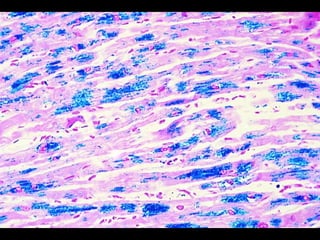

ACUMULACIONES PROTEICAS •- PROTEÍNASESTRUCTURALES : acumulación de prequeratina y otros filamentos intermedios en el citoplasma de los hepatocitos (cuerpos de Mallory) en la enfermedad hepática alcohólica . Acumulación de proteínas asociadas a microtúbulos y neurofilamentos en la enfermedad de Alzheimer (maraña neurofibrilar).- •- PROTEINURIA: reabsorción de proteínas en las nefropatías perdedoras de proteínas en los túbulos contorneados proximales .-